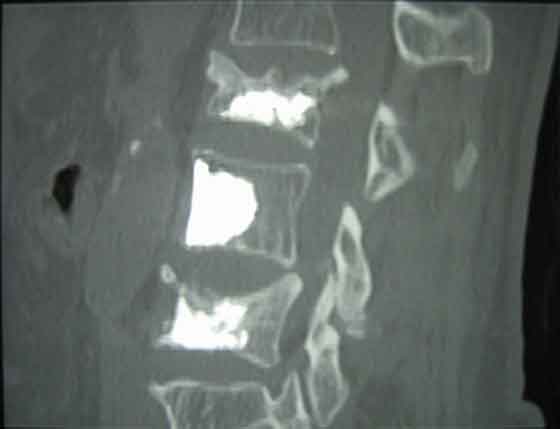

Si tratta di un sistema che ”utilizza una cannula direzionale che viene impiegata per creare una cavita’ all’interno del corpo vertebrale da trattare”. ”Tale cannula viene introdotta per via percutanea attraverso accesso su un solo peduncolo vertebrale e grazie alla sua manovrabilita’ l’operatore puo’ indirizzarla nelle zone lese o instabili del corpo vertebrale da trattare”.

Secondo l’azienda sanitaria tale procedura riduce i tempi di intervento in quanto la sua caratteristica dinamica permette all’operatore di effettuare un approccio monopeduncolare garantendo una distribuzione omogenea del cemento nel corpo vertebrale (osteoprotico) o patologico. La facilita’ di esecuzione della procedura consente l’attuazione anche in anestesia locale o spinale, in alternativa all’anestesia generale.

”E’ una tecnica indicata nei pazienti con crolli vertebrali da trauma che necessitano di una ristrutturazione vertebrale _ hanno fatto sapere gli operatori sanitari – per un’adeguata stabilizzazione del rachide. Anche le frequenti fratture vertebrali in soggetti anziani osteoporotici possono essere trattati con tale sistema”.